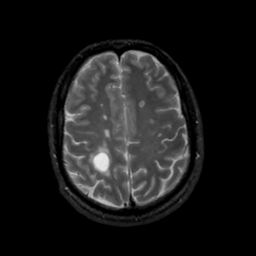

MR Study #8, March 31, 1991 -- Slice #37